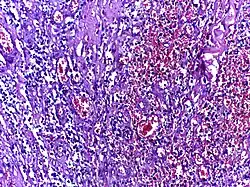

Glioblastoma | Biopsy specimen of a Glioblastoma showing extensive cell pleomorphism | Category: Histopathology of glioblastoma | glioblastoma |

![]() |